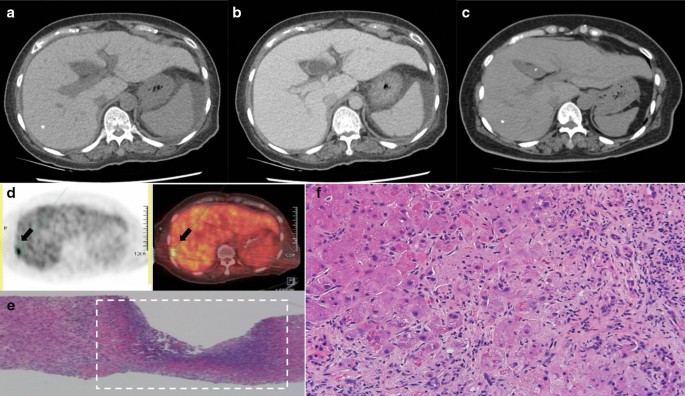

A 69-year-old woman was admitted to our hospital for postprandial epigastralgia and vomiting for 2 weeks. She had a history of diabetes mellitus and hyperlipidemia, and she had undergone bypass surgery for coronary arterial disease 2.5 years previously. She had no alcohol consumption. Initial evaluation revealed distended abdomen, epigastric tenderness, neutrophilic leukocytosis (17.3 k/μL), elevated C-reactive protein, pyuria, liver panel abnormalities (i.e., hepatitis and conjugated hyperbilirubinemia), and coagulopathy. At presentation, the serum levels of aspartate transaminase (AST), alanine transaminase (ALT), total bilirubin, direct bilirubin, albumin, and international normalized ratio of prothrombin time were 226 U/L, 108 U/L, 11.72 mg/dL, 6.97 mg/dL, 2.1 g/dL, and 1.44, respectively. Two months before this admission, the serum levels of AST, ALT, total bilirubin, and direct bilirubin were 144 U/L, 131U/L, 0.64 mg/dL, and 0.21 mg/dL, respectively. The AST to platelet ratio index (APRI) score was 2.04, an increase from 1.23 in 2 years. A hepatopathy screening including viral hepatitis (hepatitis B, C, D, and E), auto-immune and hereditary liver disease was negative, except a document of remote hepatitis A infection. Computed tomography (CT) scanning disclosed hepatomegaly, periportal edema, and ascites (Fig. 1a, b). Notably, a diffuse increase in hepatic attenuation density, a hallmark of iron or amiodarone deposition, was observed. Amiodarone had been prescribed at a daily dose of 400 mg (estimated total cumulative dose exposure of 360 g) since the bypass surgery for tachyarrhythmia. Liver attenuation was approximately 50 Hounsfield units (HU) before exposure to amiodarone (Fig. 1c) and had increased one-fold by the following year. Amiodarone was discontinued upon admission. Broad-spectrum antibiotics were used to treat a documented vancomycin-resistant enterococcal urinary tract infection and other potential occult infections without significant clinical improvement. Leukocytosis persisted and a fluorodeoxyglucose (FDG)-positron emission tomography (PET) scan 3 weeks after admission revealed multiple areas of active inflammation within the liver (Fig. 1d). The pathological findings of a targeted biopsy of the largest hot spot (Fig. 1d, arrow) in the FDG-PET scan revealed multifocal necrotizing suppurative microabscesses accompanied by aggregates of granulation tissue and histiocytes (Fig. 1e). No pathogen was observed on acid-fast, periodic-acid-Schiff, and Grocott's methenamine silver staining. Moreover, the liver parenchyma demonstrated cirrhosis and regenerative nodules associated with prominent periseptal ballooned hepatocytes containing numerous Mallory-Denk bodies (Fig. 1f). The changes of selective liver panels since the initial presentation were illustrated in Fig. 2. A rare presentation of ACLF was confirmed based on the findings of amiodarone-associated chronic steatohepatitis and superimposed microabscesses. The patient’s Chronic Liver Failure Consortium (CLIF-C) ACLF score was calculated to be 69.4, and the model for the end-stage liver disease (MELD) score was high (> 30), indicating an unfavorable outcome [2] (Fig. 3). The patient’s clinical condition deteriorated, and she died of progressive liver and renal failure.

Development and diagnosis of ACLF. a–c Serial changes in hepatic signal intensity on CT imaging. High attenuation (90–100 HU) following (a) the use of amiodarone and (b) periportal edema in ACLF. c Low attenuation (50 HU) of liver parenchyma 2 years prior to exposure to amiodarone. d FDG-PET scanning demonstrated focal hypermetabolic hepatic lesions in both lobes, with a maximum standardized uptake value of 8.8 (arrow). e, f Histopathological examination showed (e) suppurative microabscesses (dotted frame) and (f) numerous Mallory-Denk bodies in the periseptal hepatocytes